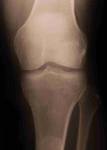

side effects and they actually destroy cartilage, the

cushioning material that protects joints. Most important,

NSAIDs do nothing to address the underlying laxity of

ligaments and tendons which is the source of chronic pain.